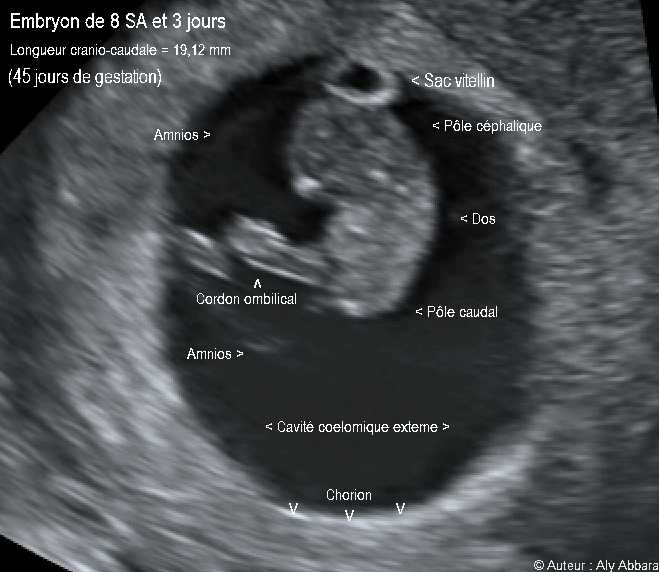

• Images échographiques montrant un embryon âgé de 45 jours de gestation (soit 8 semaines d'aménorrhée et 3 jours).

• La longueur crânio-caudale embryonnaire (LCC) = 19,12 mm

• La fréquence cardiaque calculée = 154 battements/minute.

• Ces images montrent un sac gestationnel composé essentiellement :

° d'une cavité cœlomique externe limitée par le chorion qui s'insère sur l'endomètre ; cette cavité cœlomique externe contient :

* Un sac amniotique limité par l'amnios et contenant

“ un embryon de 19,12 mm de longueur crânio-caudale avec deux pôles déjà différentiés : pôle céphalique et pôle caudal”

* Le sac amniotique juxtapose le sac vitellin qui se situe dans la cavité cœlomique externe.